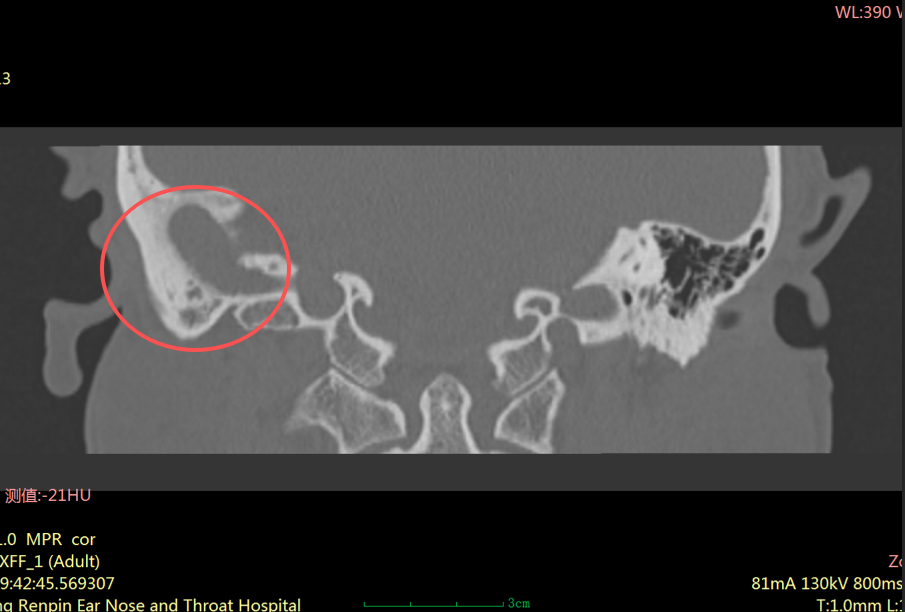

“患者右耳中耳腔已形成胆脂瘤,它像一颗不断侵蚀听骨的‘定时炸弹’,若再拖延,可能引发面瘫、颅内感染等严重并发症。”耳科主任张朝梅指着CT影像解释道。

虽然它不是肿瘤,但危害却不容小觑。它会像“寄生虫”一样,不断破坏周围的骨质,可能侵犯中耳的听小骨、面神经管、半规管等重要结构,进而导致听力下降、耳鸣、面瘫,严重时甚至可能引发颅内感染,危及生命。